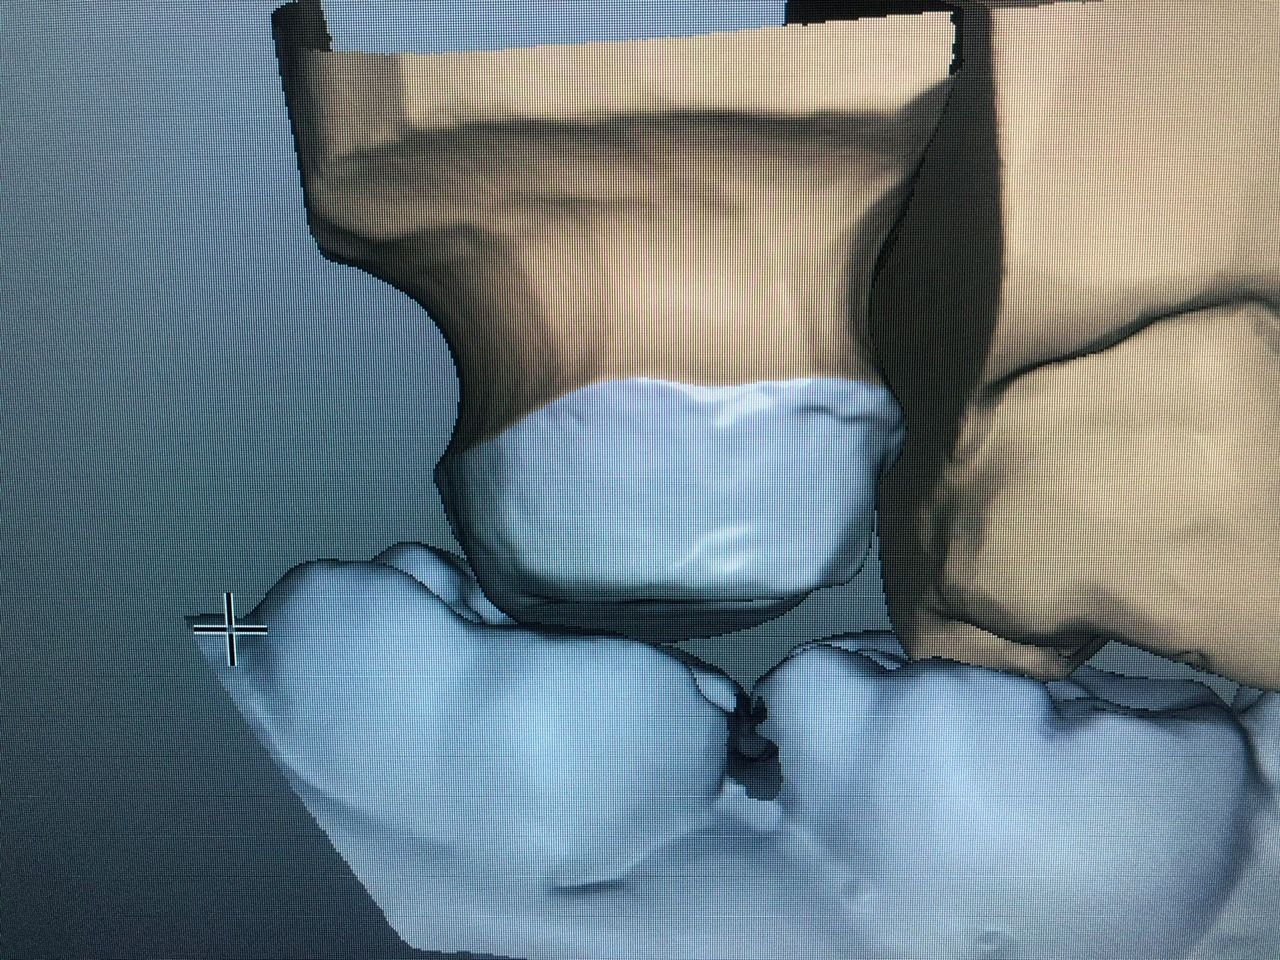

Avvalendoci di validi collaboratori e strumenti all'avanguardia, da Studio Dentistico Amerio ad Ala forniamo servizi specialistici di odontoiatria infantile, chirurgia parodontale, implantologia osteointegrata ed estetica dentale.

Inoltre consigliamo controlli frequenti e periodici associati a detartrasi annuale e, quando necessario, trattamenti dentistici su misura, come lo sbiancamento con laser odontoiatrico, la cura delle malattie gengivali, l'applicazione di faccette in ceramica e le terapie di ortodonzia con apparecchio dentale.